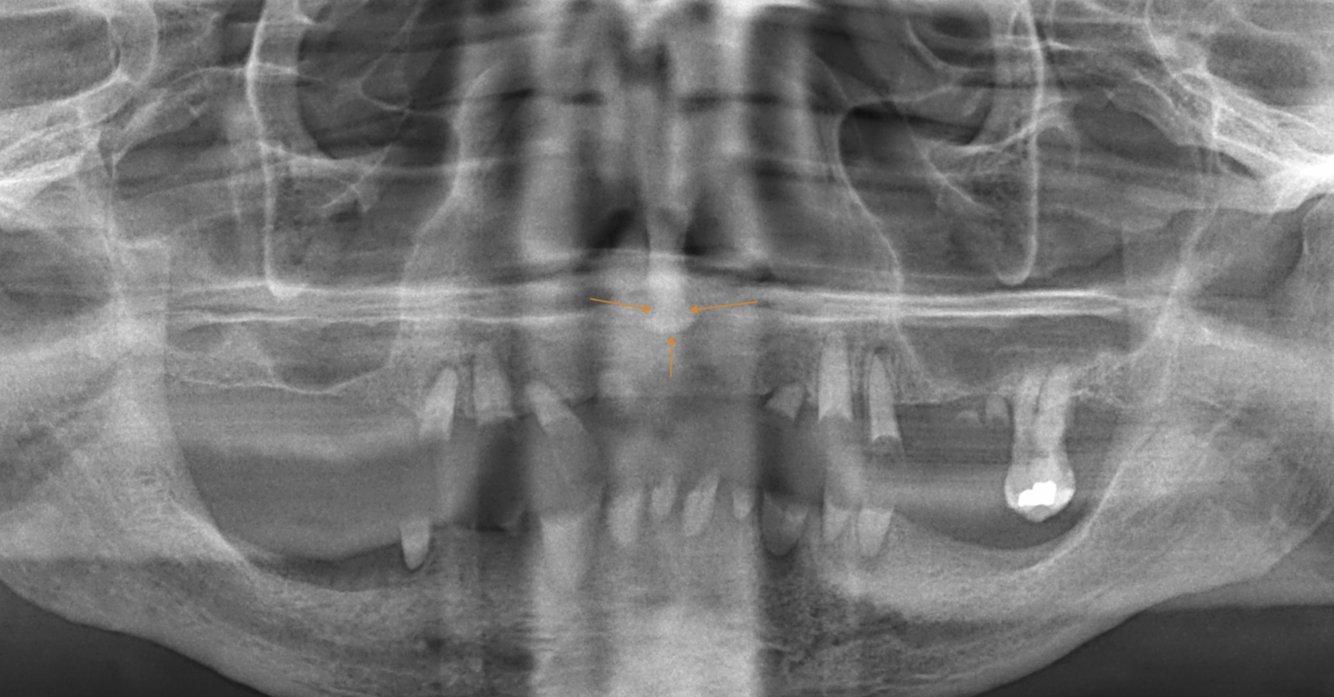

What does the red indicate in the following image?

Lingual foramen